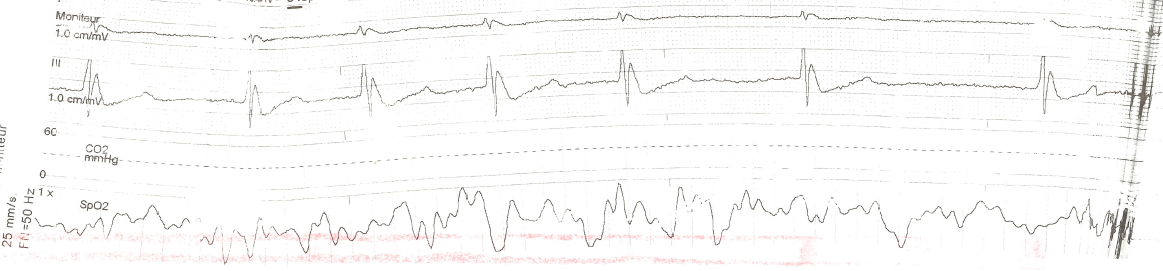

Cet ECG 3 dérivations est celui d’un patient en hypothermie accidentelle sévère en préhospitalier et montre une bardycardie et onde J’Osborn.

Le terme onde J désigne la formation d’une onde lorsqu’il existe une surélévation du point J par rapport à la ligne de base de plus de 1 mm, présente sur deux dérivations consécutives. Cette onde forme un crochetage de la branche terminale du QRS, avec surélévation en dôme.

En cas d’hypothermie, l’onde J est le plus souvent retrouvée II, III, aVF, V3-V6 sur un ECG 12 pistes. Son incidence varie dans l’hypothermie, de 50 à 80 % des cas, jusqu’à 100 % lors d’hypothermie sévère (< 28°) selon les séries. Son amplitude et sa présence seraient inversement proportionnelles à la profondeur de l’hypothermie mais influencées également par d’autres facteurs (l’acidose par exemple).

Image proposée par Christophe Apothéloz (SPSL) et Perrine Truong (CHUV).